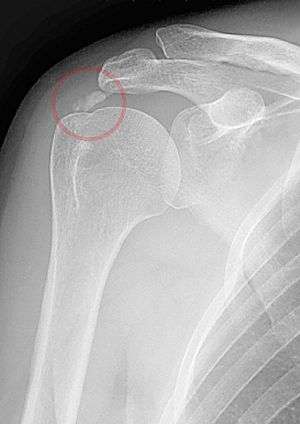

A plain X ray of the shoulder showing calcific tendinitis | |

The calcific deposits are visible on X-ray as discrete lumps or cloudy areas. The deposits look cloudy on X-ray if they are in the process of reabsorption, and this is also when they cause the most pain. The deposits are crystalline when in their resting phase and like toothpaste in the reabsorptive phase. However, poor correlation exists between the appearance of a calcific deposit on plain X-rays and its consistency on needling. Ultrasound is also useful to depict calcific deposits and closely correlates with the stage of disease.[1]